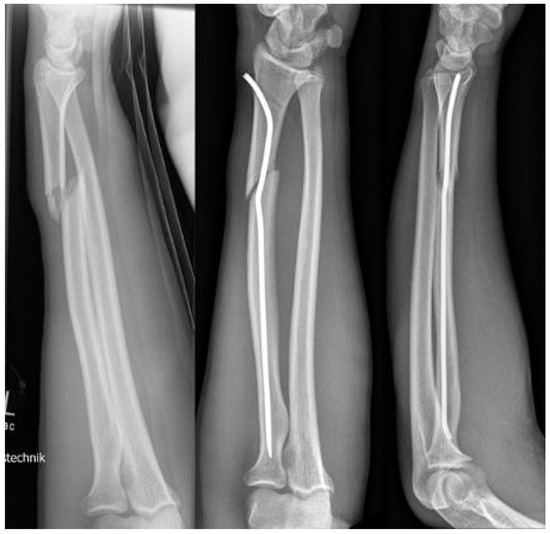

Scheme 2. 2-year-old boy with secondary displacement.

Scheme 3. 17-year-old boy.